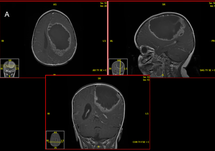

We talked about how precise proton treatment can be, but because we can direct it, we can make it stop exactly where we want to and that reduces the radiation exposure to normal areas of the brain. But if we can’t find or localize the treatments, then it’s like we don’t have a sight on our sniper rifle. We have this super precise machinery, but without the best imaging, we may not be able to take full advantage of the capabilities of this highly accurate machine. So we’ve also been studying different ways that we can find tumors that are hiding in our traditional imaging, most tumors are found with CT’s or MRIs, but in radiation oncology, we’ve learned over many years of studying tumors and how they regrow or recur that there are often fingers or tentacles of the tumor that we can’t see that are, kind of, the root system of the tumor that we can’t see mixed in with normal brain or normal muscle or normal bone, depending on where the tumor is.

There are advanced treatments, specialized PET scans, for example. We use amino acid PET scan called F-DOPA that we have been able to use to see brain tumors, for example, that are hidden in normal brain that are not visible on MRI. There are other advanced types of MRIs where things are done to find areas of high blood flow or changes in basically the pressure or elasticity that would suggest there’s other things beside normal muscle mixed in with the muscle that you’re seeing on an MRI elastography, so there are newer imaging techniques that help us take full advantage of the highly accurate and precise radiation that we’re able to do now.

The other thing that we’re using, and people have heard a lot about this recently, is artificial intelligence or machine learning neural networks. Basically, we’re using machines to help us look at scans and see things that aren’t visible to the naked eye. So we can train computers, it’s called radiomics when we are training radiographic images, we can train computers to look through multiple different features of MRIs and tell us that there’s something hiding in this area of the MRI that we can’t see with the naked eye. And it can tell us things about the aggressiveness of a tumor, how quickly it’s dividing based on the different densities that it’s seeing that we can’t see. We’ve been able to use radiomics to tell us, even without a biopsy what type of brain tumor it is or how aggressive the sarcoma is, tell us genetic features. We’ve learned that some tumors have certain genetic features that predict their responsiveness to radiation or chemotherapy and now we’re able to use radiomics to look at these MRIs and say, ‘There’s a 90% chance that this tumor has these gene deletion, which means it’s going to be much more sensitive to radiation and/or chemotherapy’.